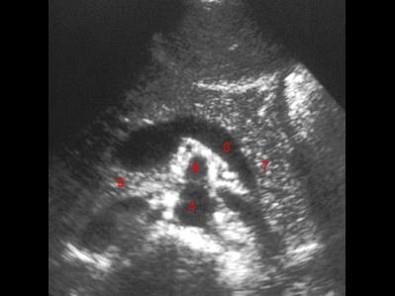

图示6所指部位?(?)A.脾静脉B.腹主动脉C.胰尾D.肠系膜上动脉E.肠系膜上静脉

问题 图示6所指部位?(?)

选项 A.脾静脉 B.腹主动脉 C.胰尾 D.肠系膜上动脉 E.肠系膜上静脉

答案 D